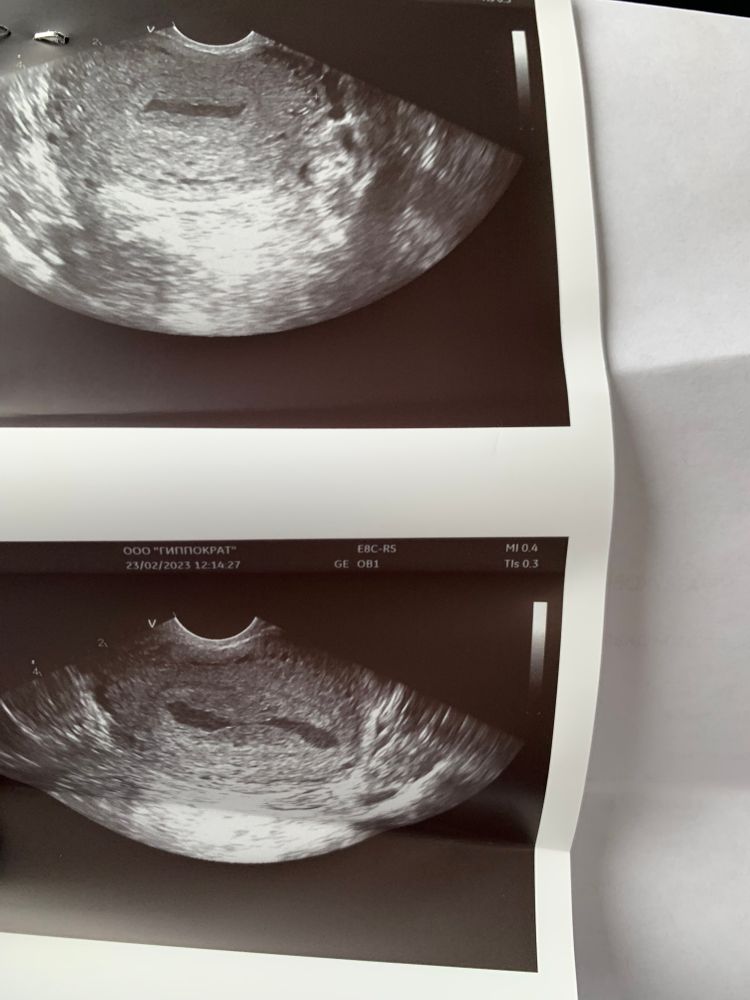

планирую беременность Краснодар

Милена, в матке и нигде ничего нет, сегодня полчаса по несколько раз смотрела, и сверху и вагинально…ничего…. Единственное есть жидкостное содержимое в матке

Ангелина, неизвестно. Сказали по всей полости матки Изображение

Pasernes, похоже на серозометру(((. А у вас раньше это было? Вам бы гистероскопию сделать. Эта штука не очень хорошо